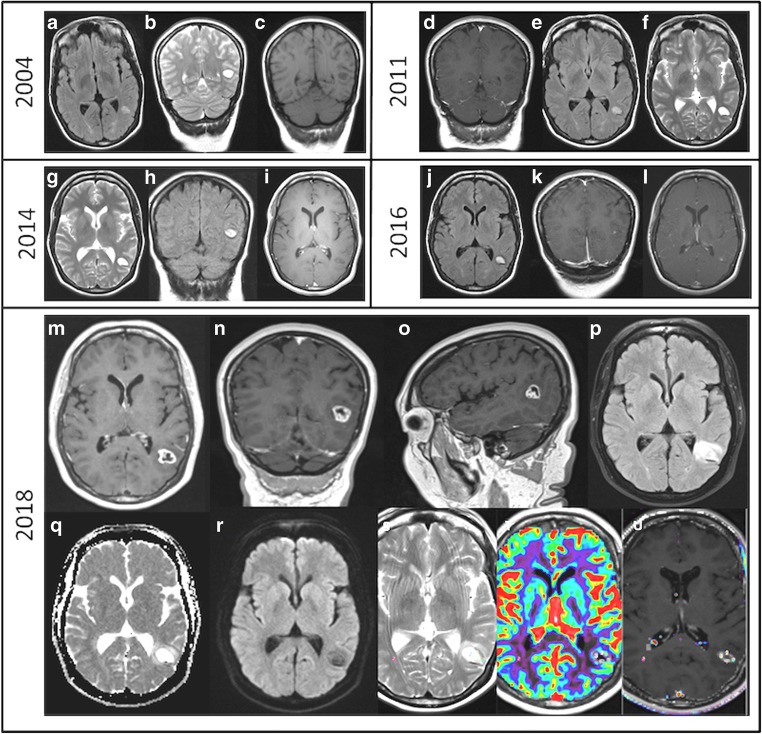

A 49-year-old right-handed bilingual lady (primary language Tamil, and secondary language English) was referred to our neuro-oncology department for follow-up of a lesion located in the posterior aspect of the left temporal lobe (temporo-occipital junction). She was incidentally diagnosed in 2004 (from image investigations for headaches) with a left temporal lobe lesion, and it was decided to monitor the lesion with regular clinical and imaging follow-up (Fig. 1a–c). The lesion remained stable until 2016 (Fig. 1d–i), when the lesion showed focal contrast enhancement (Fig. 1j–l). The patient continued to be asymptomatic, but as the lesion showed signs of progression, surgical treatment was offered, but was declined.

Fig. 1.

Evolution of the temporal-parietal-occipital lesion from 2004 to 2018. Slow growing lesion since 2004 with initial punctiform contrast uptake in 2016 that increased in size in 2018. 2004 (a, axial FLAIR; b, coronal T2; c, coronal T1); 2011 (d, coronal T1 GAD; e, axial FLAIR; f, axial T2); 2014 (g, axial T2; h, coronal FLAIR; i, axial T1 GAD); 2016 (j, axial FLAIR; k, coronal T1 GAD; l, axial T1 GAD); 2018 (m, axial T1 GAD; n, coronal T1 GAD; o, sagittal T1 GAD; p, axial FLAIR; q, ADC map; r, DWI; s, axial T2, t, u, CBV)

Two years later, she remained asymptomatic, but imaging of the lesion revealed further signs of transforming lesion with ring contrast enhancement, increased vasogenic oedema and perfusion (Fig. 1m–u). At this stage, the patient accepted the surgical treatment.